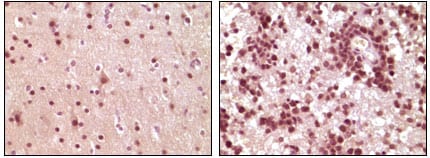

分类: 科研抗体货号: 20101别名: ELK1应用: IHC反应种属: Human